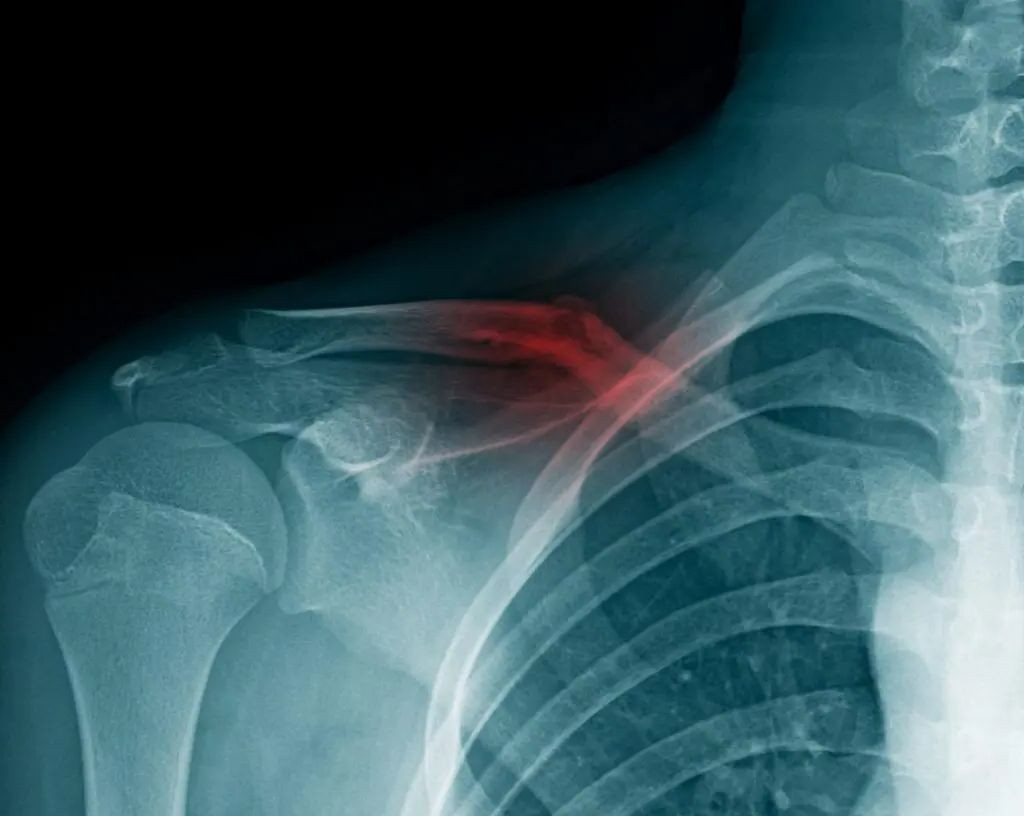

Перелом ключицы

Перелом ключицы — это повреждение кости, которая соединяет грудину с лопаткой и укрепляет плечевой пояс. Травма вызывает сильную боль и неспособность полноценно двигать рукой.

Как правило, после проведения визуального осмотра диагноз не вызывает сомнений. Однако для получения точной информации о характере травмы и выборе лечебной тактики необходимо пройти рентгенологическое обследование, которое считается «золотым стандартом» в диагностике перелома ключицы. В некоторых случаях для исключения возможного повреждения мягких тканей может быть назначено КТ или МРТ.